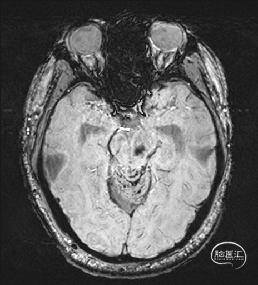

5.术后72小时复查磁共振提示海绵状血管瘤全切。

术后72hMRI复查

1.完成手术目的,“一箭双雕”,既切除了海绵状血管瘤,又缓解了脑积水;

2.术后面部麻木及右上肢麻木明显缓解,出院时仅右手指麻木;

3.头痛等颅高压症状缓解;复视无明显缓解;

4.无新发神经功能障碍;